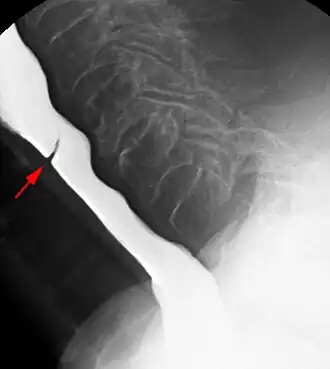

Esophageal web stenosis in barium swallow examination lateral view.

Esophageal web stenosis in barium swallow examination lateral view. -